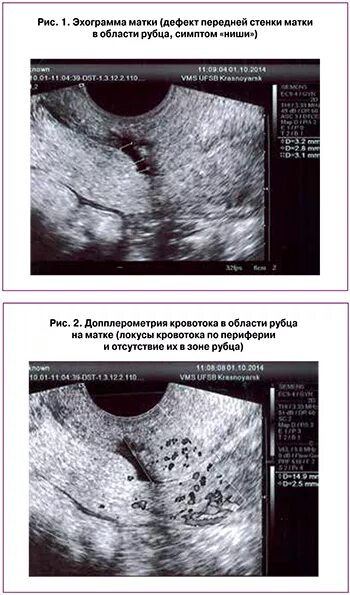

Рубец на матке мкб